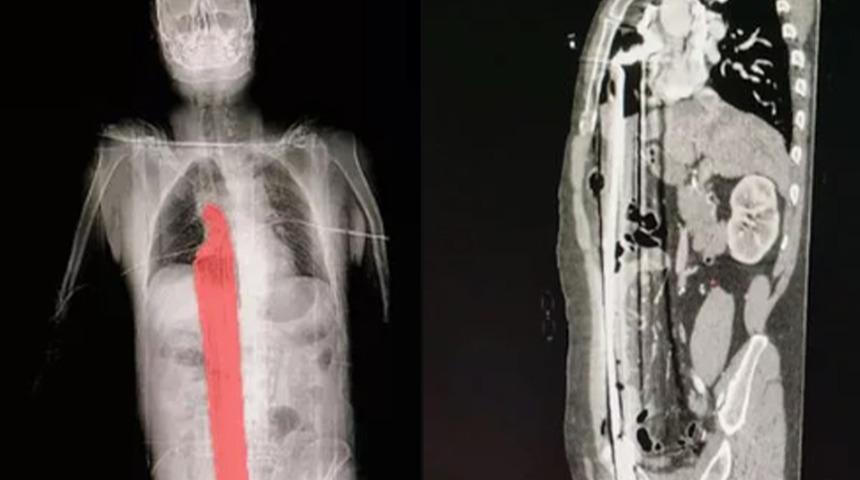

MYNET|DIŞ HABERLER Brezilya'da bir inşaatta görev yapan ismi açıklanmayan 57 yaşındaki bir adam 5 metre yüksekten düştü ve 60 cm uzunluğundaki demir çubuğa saplandı. Röntgen görüntüleri demir çubuğun anüs ve skrotum arasındaki bölge olan perineumunu delindiğini gösterdi. Çubuk daha sonra gövdesinden yukarı çıktı ve karaciğerine ve diyaframın bir kısmına girdi ancak kalbini kıl payı ıskaladı.

Adam acil tedavi için hastaneye kaldırıldı. Cerrahi operasyonlarla çubuk gövdesinden çıkartıldı.

İyileşen adam 3 gün sonra yoğun bakımdan çıkartılırken yerel yetkililerin son derece nadir olarak tanımladığı korkunç olaydan 12 gün sonra hastaneden taburcu edildi.